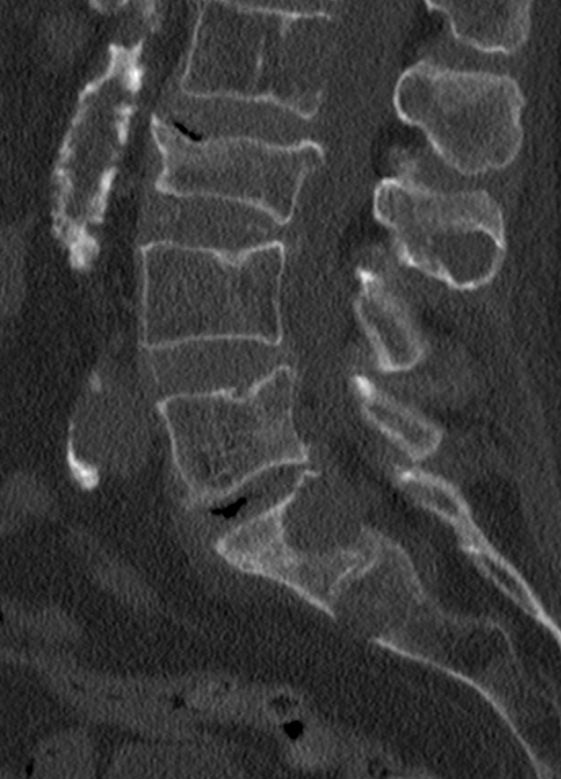

82-jährige Frau mit einem Leiomyosarkom der Vulva rechts pT2a N0 M0, V1, G2.

Klinik: Vulva-Tumor rechts. Der Tumor ist relativ glatt begrenzt und gut 5 cm groß; er ist auf dem absteigenden Schambeinast beweglich und reicht dicht bis an die Urethralöffnung heran.

Makroskopie: subepidermal gelegenes Leiomyosarkom. Zentral gelegen ein die Haut vorwölbender, 6,5 cm messender Tumor.

Mikroskopie: Subepithelial in Zügen und Bündeln angeordnete, teils epitheloide und teils spindlige Tumorzellen. Oftmals längsovale Zellkerne mit abgestumpften Kernenden. Daneben Areale mit erheblicher Zell- und Kernpolymorphie. Ausbildung bizarrer Riesenkerne. Schmaler Zytoplasmasaum. Herdförmige Tumornekrosen mit vitalen, um Blutgefäße angeordneten Tumorzellen und weiter entfernt gelegenen nekrotischen Arealen. Ausbildung von Tumorriesenzellen. Oftmals Apoptosen. Einzelne Tumoreinbrüche in Blutgefäße.

Immunhistochemie: Deutliche Expression von Alpha Aktin und Caldesmon. S 100-Protein, CD 117, CD 34 und DOG1 Immunhistochemisch negativ. Ki 67 40 %.

Hemivulvektomie rechts, R1-Resektion basal und medial. Brachytherapie.

8 Monate nach Primärtherapie auftreten von Knochenmetastasen. Kein lokales Rezidiv.